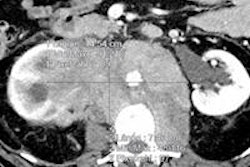

At the same congress, another German group showed that 3D volumetry methods can allow radiologists to provide oncologists with more precise information on tumor response to therapy, including calculation of the important prognostic factor of early tumor shrinkage. Dr. Anno Graser from Munich discussed how semiautomated volumetry techniques offer reproducibility benefits and reduce misclassification of therapy response. Go to our Advanced Visualization Digital Community, or click here.